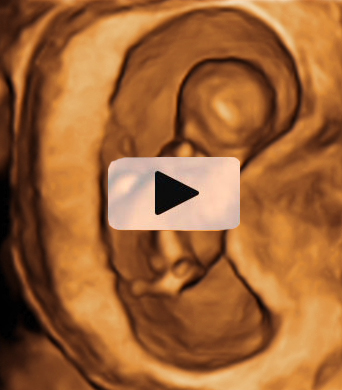

Ecografía Embarazo 4D Semana 12 - PRUEBAS DIAGNÓSTICAS